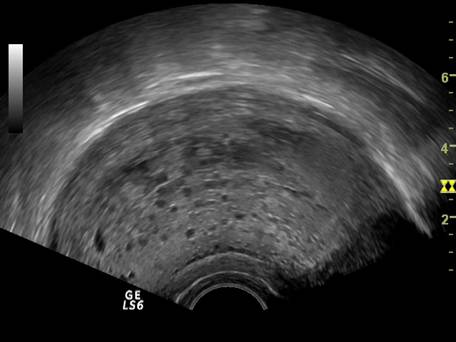

Fig. nr. 82 Ou clar la ecografia transvaginala